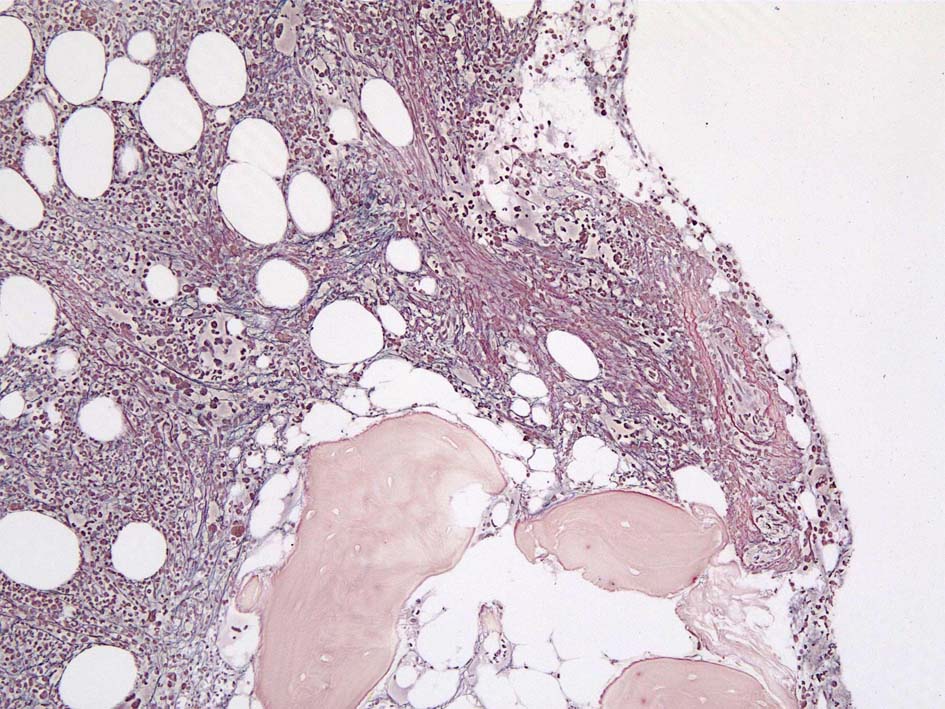

CD42b染色

黒染する弾性線維の増生のほか, 赤く染まる膠原線維の増生が確認される. MF-2 fibrosis. 鍍銀染色の核染色をすると膠原線維の赤染がわからなくなるので行わない.